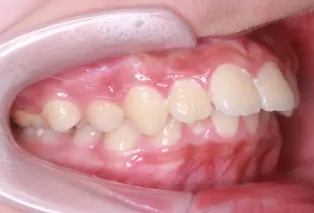

Intraoral photos after treatment